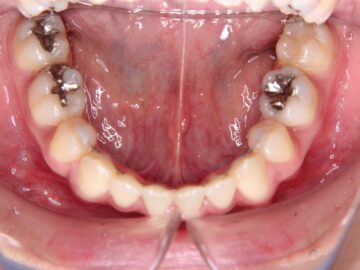

ご相談時

| 抜歯部位 | 上顎左右測第一小臼歯、下顎左右測第一小臼歯 |

| 治療のリスク | 歯肉退縮、ブラックトライアングルの出現 |